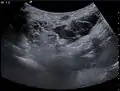

يتم تشخيصها عن طريق التصوير بالموجات فوق الصوتية قبل الولادة.

الورم الرطب الكيسي بالموجات فوق الصوتية أثناء الحمل